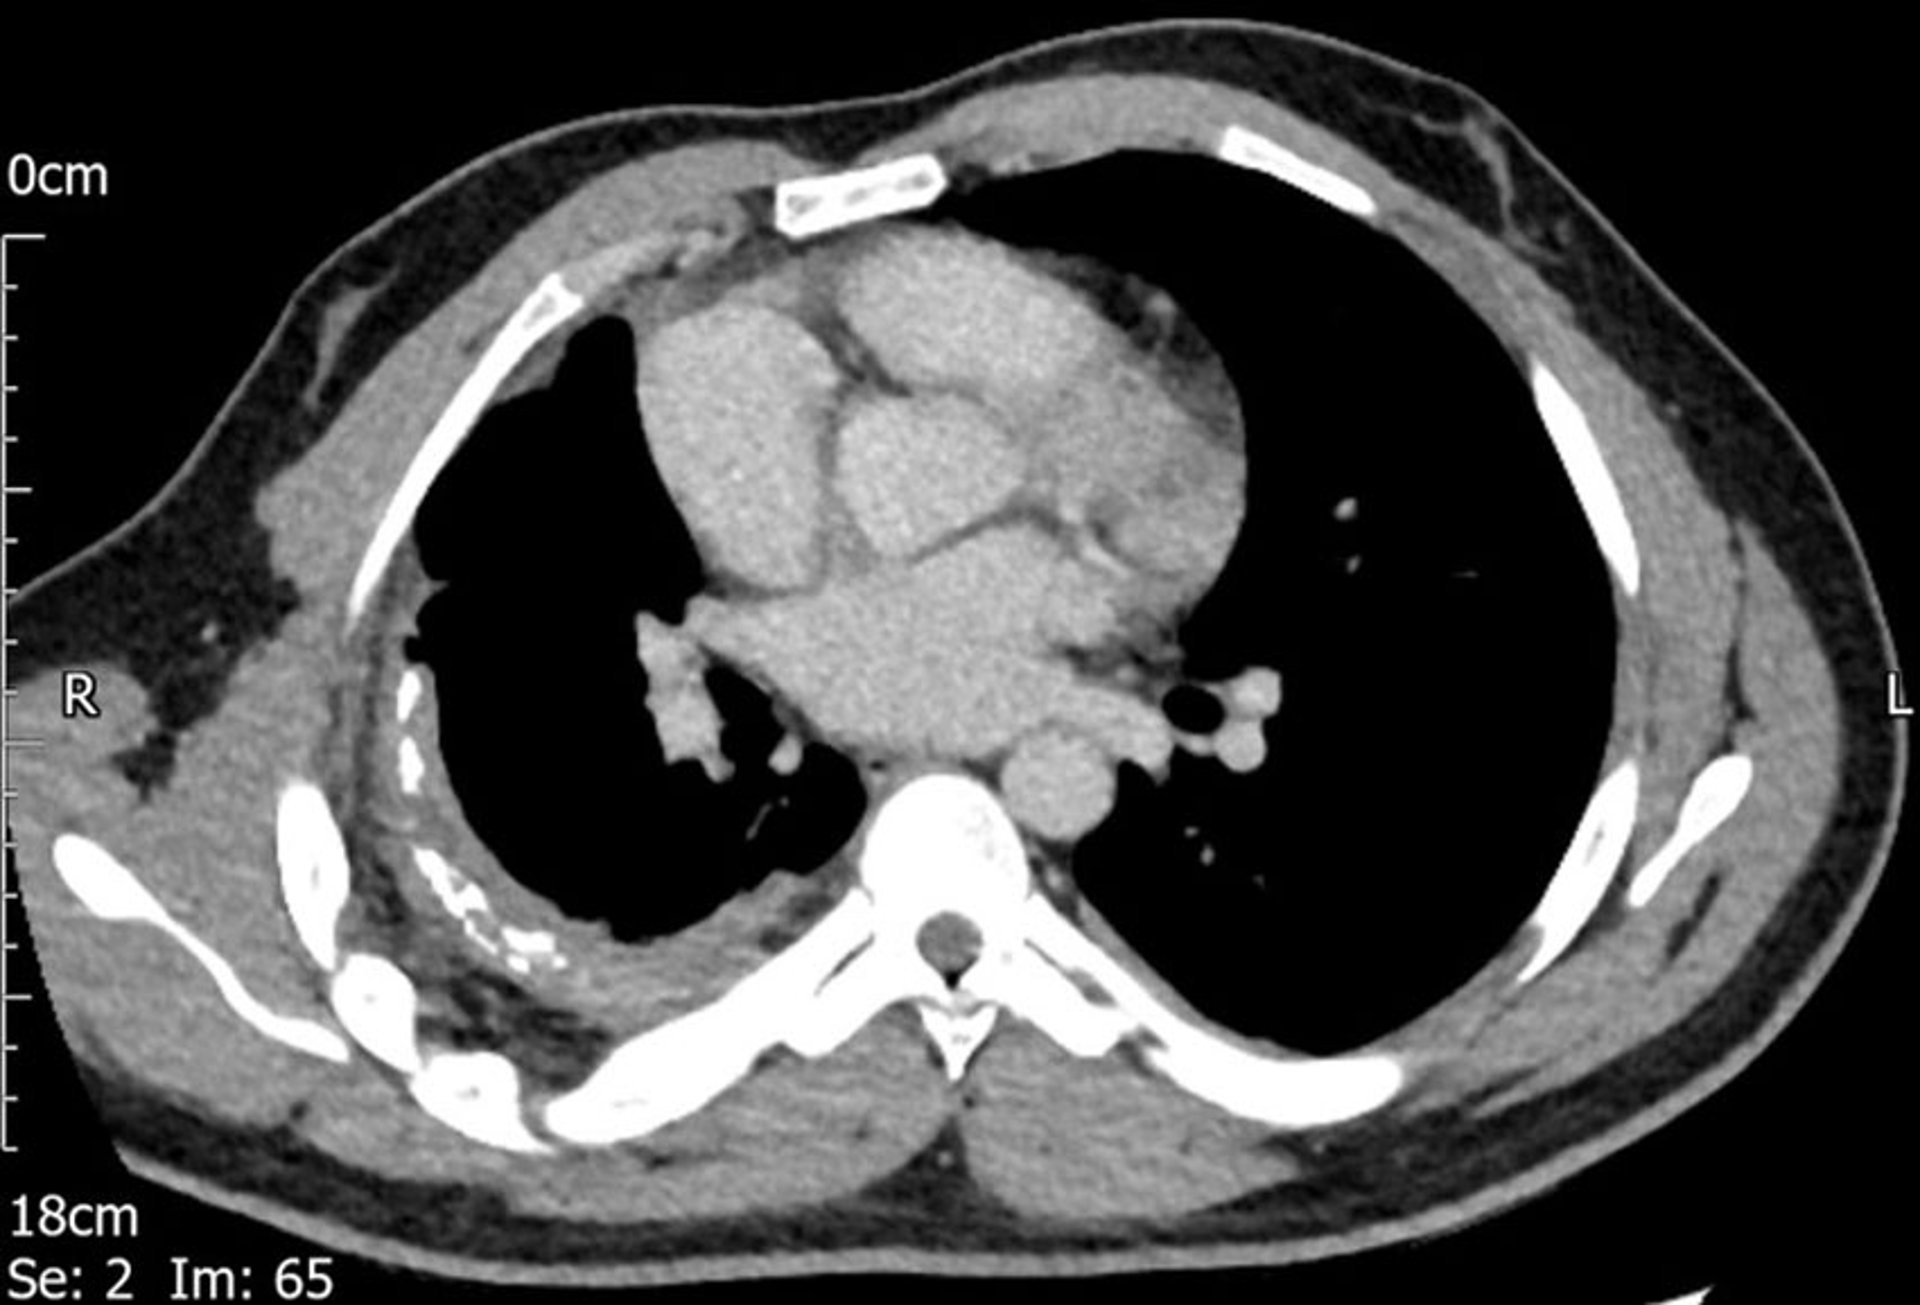

En esta TC se observa engrosamiento pleural en el lado derecho.

Image courtesy of Najib M. Rahman, BMBCh MA (oxon) DPhil.